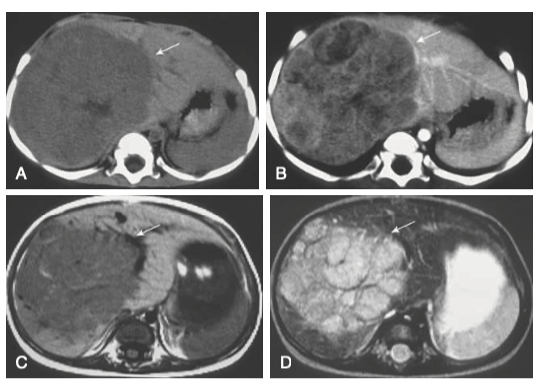

• 영상검사: 복부 초음파, CT, MRI 및 흉부 CT